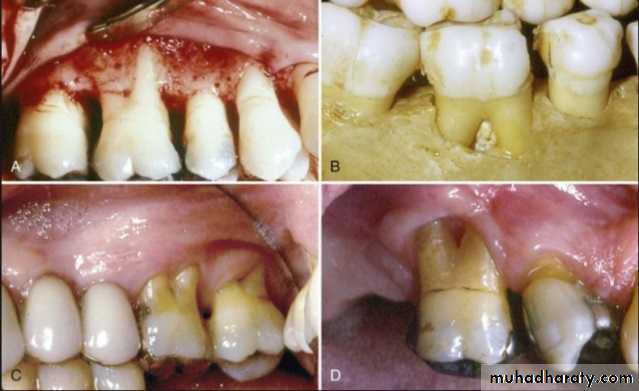

Evaluation of periodontium

Periodontal disease is one of the main etiologic factors in the loss of the teethA removable partial denture placed in the presence of active periodontal disease will contribute significantly to the rapid progression of the disease and the loss of the remaining teeth.

The causative factors must be eliminated, the disease process must be controlled before the fabrication of the prosthesis.

Examination findings that indicate possible need for periodontal treatment include

Pocket depth in excess of 3 mmFurcation involvement

Deviations from normal color and contour in gingiva, indicating gingivitisMarginal exudate

Potential abutment teeth with less than 2 mm of attached gingiva

Pulling of muscle or frena on attached gingiva

Evaluation of oral mucosa

Pathologic changes:Any ulceration, swelling , or color change that might indicate malignant or pre malignant changes should be recognized and evaluated through biopsy or referral.

Palatal papillary hyperplasia:

Caused by inflammatory response in the sub mucosa, consists of numerous papillary growths.Food debris, fungi, bacteria collect in the crevices and may give rise to secondary infection.

If the patient will not be able to keep the lesion adequately clean, it should be removed.

• Tissue reactions to the wearing of a prosthesis

Epulis fissuratum: denture granuloma

It is a tumor like hyperplasic growth caused by an ill- fitting or overextended border of removable prosthesis

It may occur in double fold of tissue with one fold on the tissue side and one on the polished side of the denture border

Surgical removal – formation of scar tissue - not good for proper border seal

If the irritation is removed – resolves on its own4/2/2018